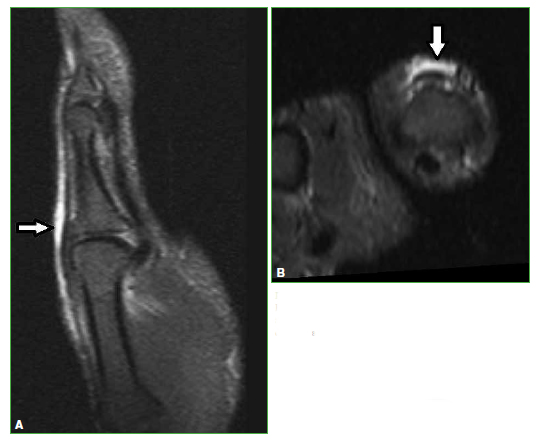

Figura 11.

Resonancia magnética de rodilla, secuencia STIR. Cortes axial (A) y sagital (B). Lesión focal en la inserción distal del semimembranoso después del esfuerzo durante la competencia (flechas).